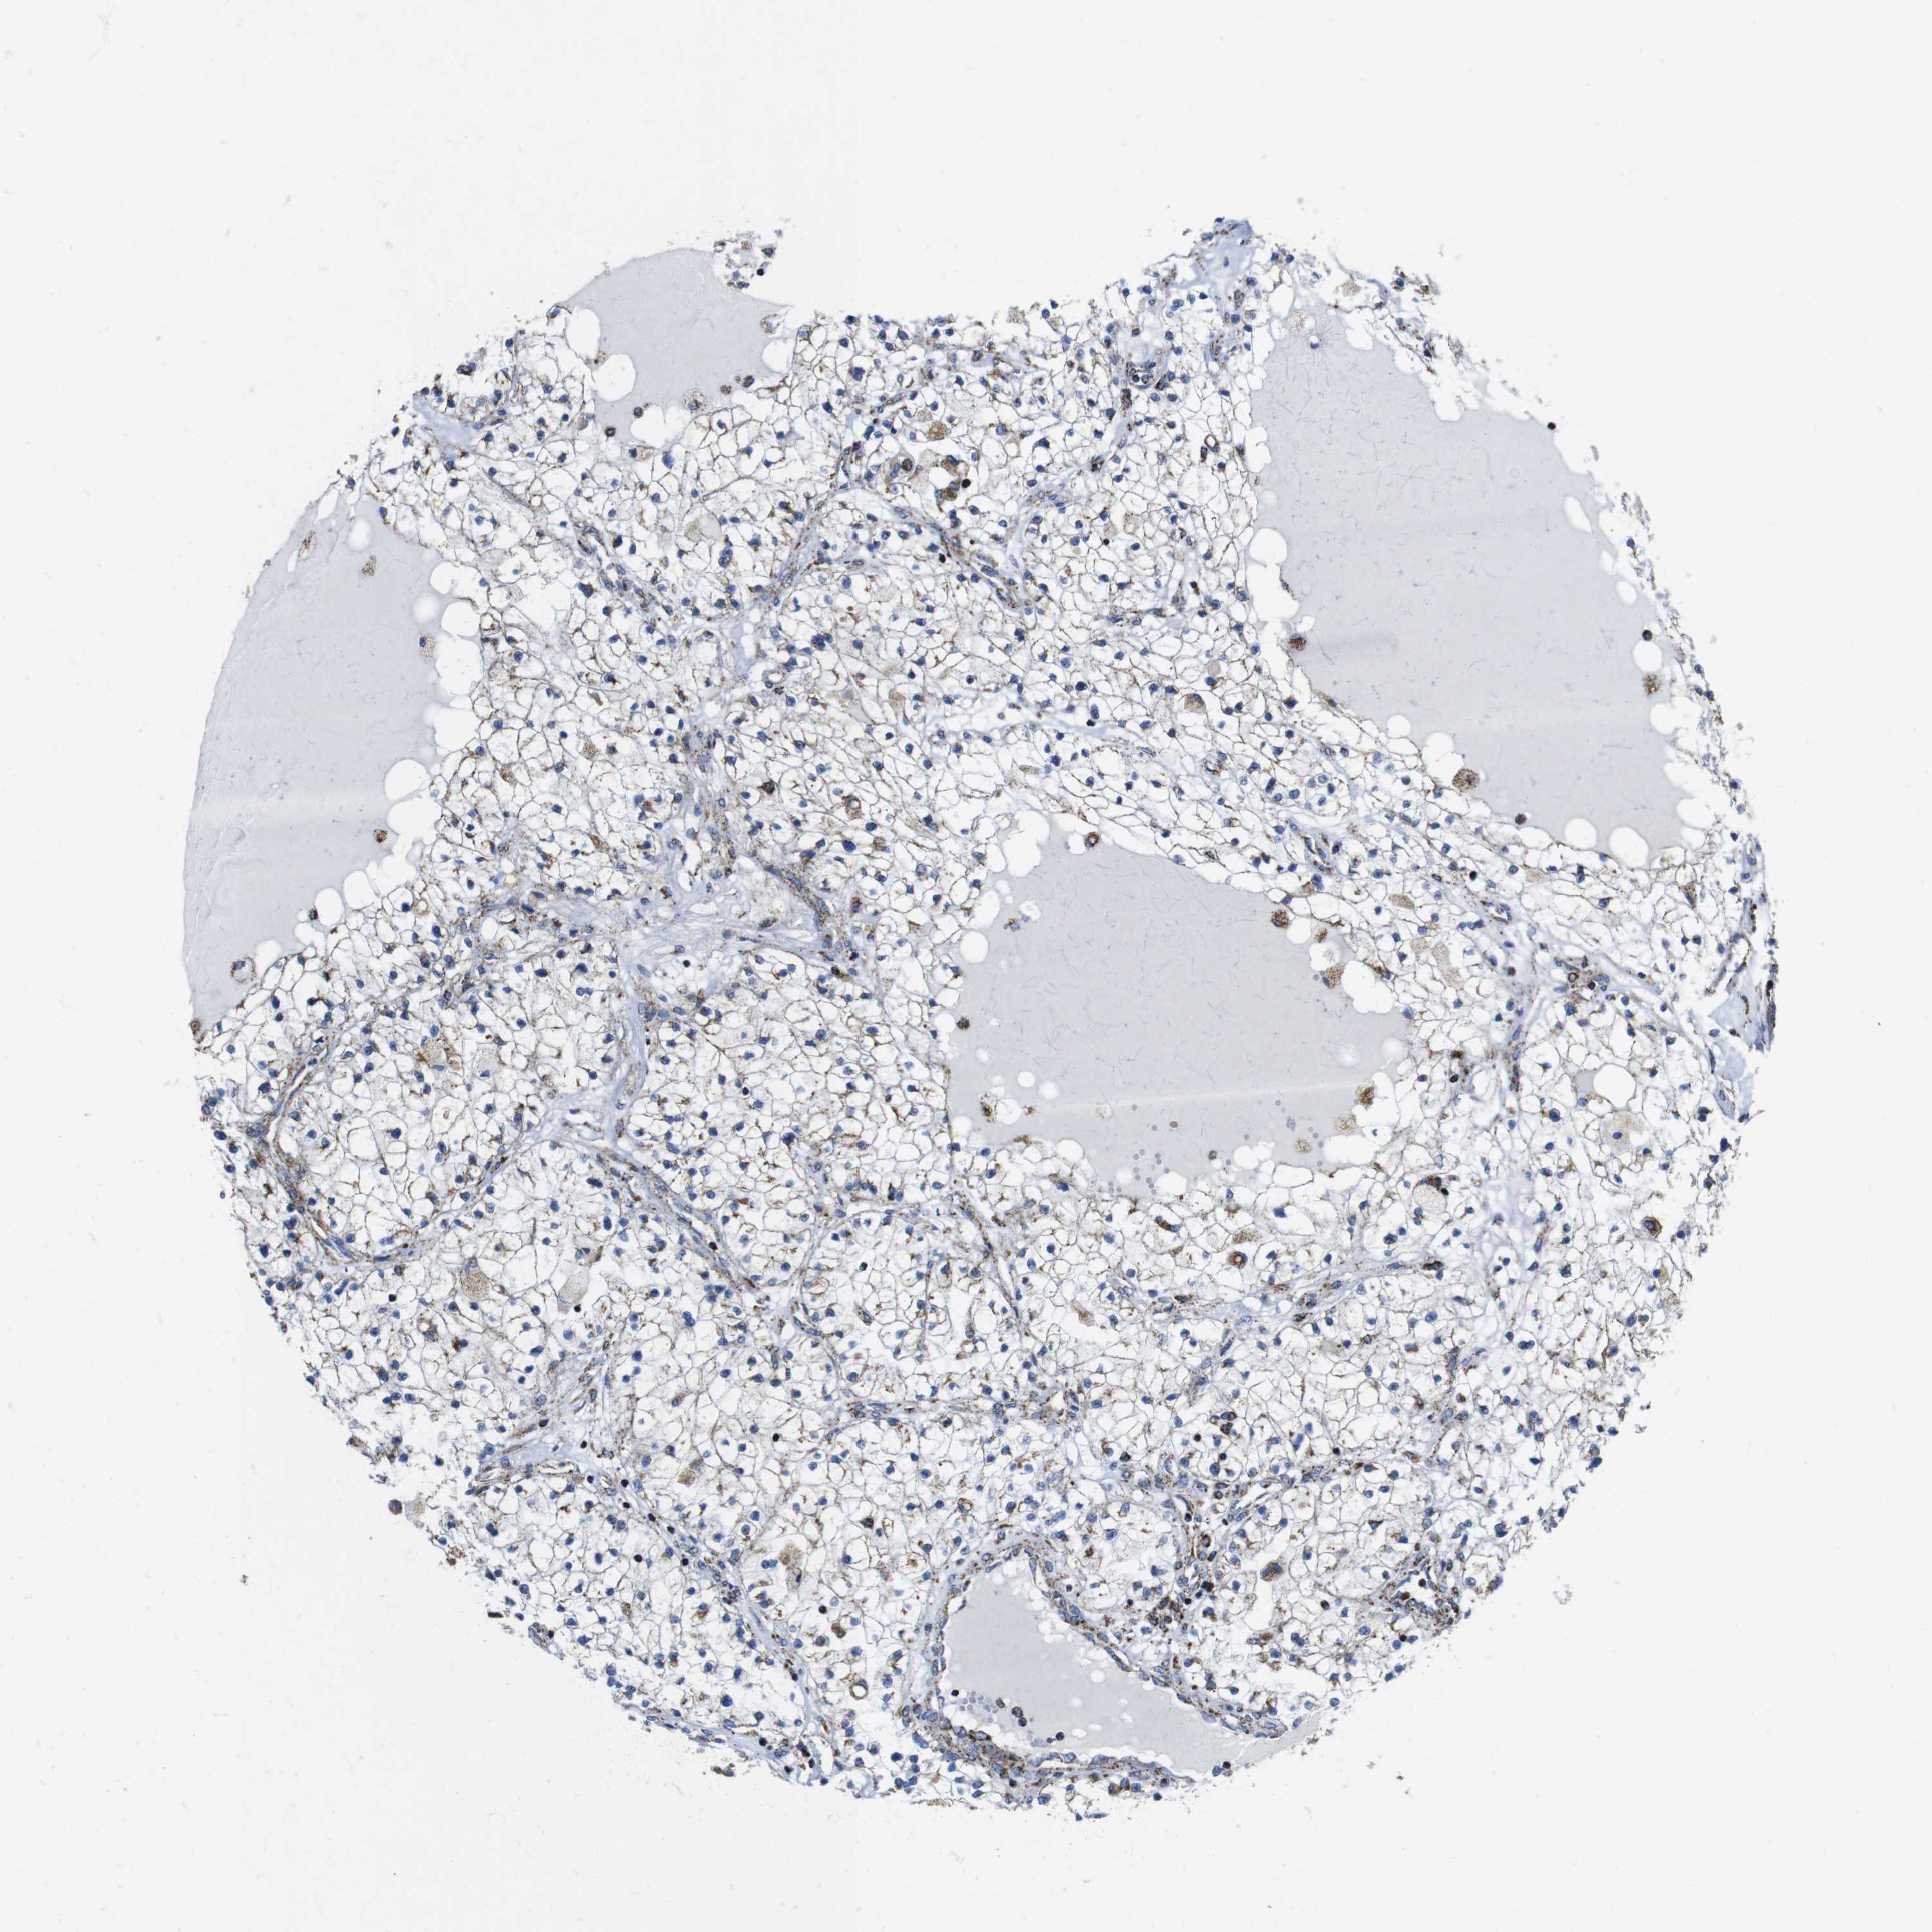

KIDNEY RENAL CLEAR CELL CARCINOMA (VALIDATION) - Interactive survival scatter ploti

The Survival Scatter plot shows the clinical status (i.e. dead or alive) for all individuals in the patient cohort, based on the same data that underlies the corresponding Kaplan-Meier plots. Patients that are alive at last time for follow-up are shown in blue and patients who have died during the study are shown in red.

The x-axis shows the expression levels (FPKM) of the investigated gene in the tumor tissue at the time of diagnosis. The y-axis shows the follow-up time after diagnosis (years). Both axes are complimented with kernel density curves demonstrating the data density over the axes. The top density plot shows the expression levels (FPKM) distribution among dead (red) and alive patients (blue). The right density plot shows the data density of the survived years of dead patients with high and low expression levels respectively, stratified using the cutoff indicated by the vertical dashed line through the Survival Scatter plot. This cutoff is automatically defined based on the FPKM cutoff that minimizes the p-score. The cutoff can be changed by dragging the vertical line or by entering a cutoff value in the square labeled "Current cut-off".

Under the Survival Scatter plot the p-score landscape (black curve; left axis) is shown together with dead median separation (red curve; right axis). Dead median separation is the difference in median mRNA expression between patients who have died with high and low expression, respectively. It is calculated as follows: median FPKM expression of dead patients with high expression - median FPKM expression of dead patients with low expression. This is intended to aid the user in visually exploring custom cutoffs and the associated p-scores and dead median separation.

Individual patient data is displayed and can be filtered by clicking on one or more of the category buttons on the top of the page. Categories describing expression level and patient information include: high, low, alive, dead, female, male and tumor stages. The scale of the x-axis can be toggled between linear and log-scale by clicking on the "x log" button. Mouse-over function shows TCGA ID, patient information and mRNA expression (FPKM) for each patient.

& Survival analysisi

Kaplan-Meier plots summarize results from analysis of correlation between mRNA expression level and patient survival. Patients were divided based on level of expression into one of the two groups "low" (under cut off) or "high" (over cut off). X-axis shows time for survival (years) and y-axis shows the probability of survival, where 1.0 corresponds to 100 percent.

TMEM192 is validated prognostic, high expression is favorable in Kidney Renal Clear Cell Carcinoma (validation)

Best expression cut offi

Based on the FPKM value of each gene, patients were classified into two groups and association between prognosis (survival) and gene expression (FPKM) was examined. The best expression cut-off refers the FPKM value that yields maximal difference with regard to survival between the two groups at the lowest log-rank P-value. Best expression cut-off was selected based on survival analysis .

When clicking on this number, the vertical dashed line indicating cut-off, the interactive survival plot, and the Kaplan-Meier curve will be adjusted to show results based on the best expression cut-off.

: 25.06

TCGA RNA samplesi

RNA-seq data is reported as average FPKM (number Fragments Per Kilobase of exon per Million reads), generated by the The Cancer Genome Atlas (TCGA) .

Normal distribution across the dataset is visualized with box plots, shown as median and 25th and 75th percentiles. Points are displayed as outliers if they are above or below 1.5 times the interquartile range. FPKM values of the individual samples are presented next to the box plot.

Average pTPM 25.2

Number of samples 100